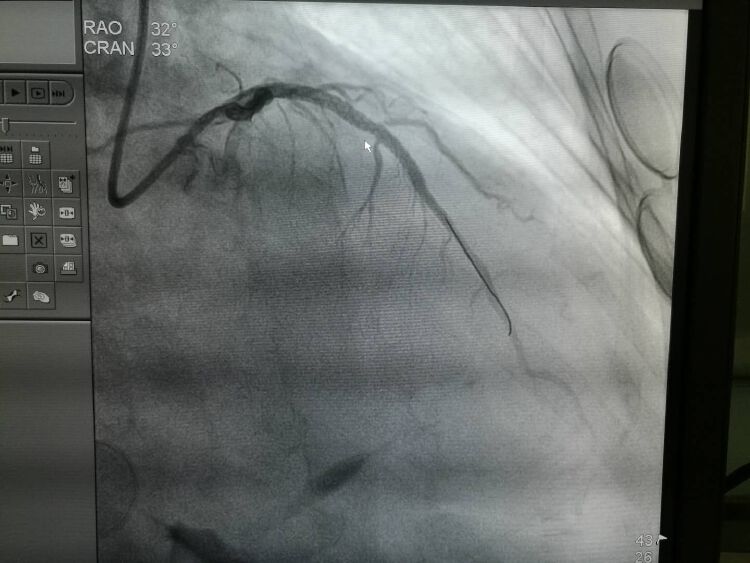

当天上午11点,据接诊医院的胸痛中心反馈,该病人造影发现前降支近断闭塞,植入2枚支架,右冠中远段重度狭窄等待二期手术。经过及时有效的救治,大叔脱离了生命危险,已安全返回CCU。